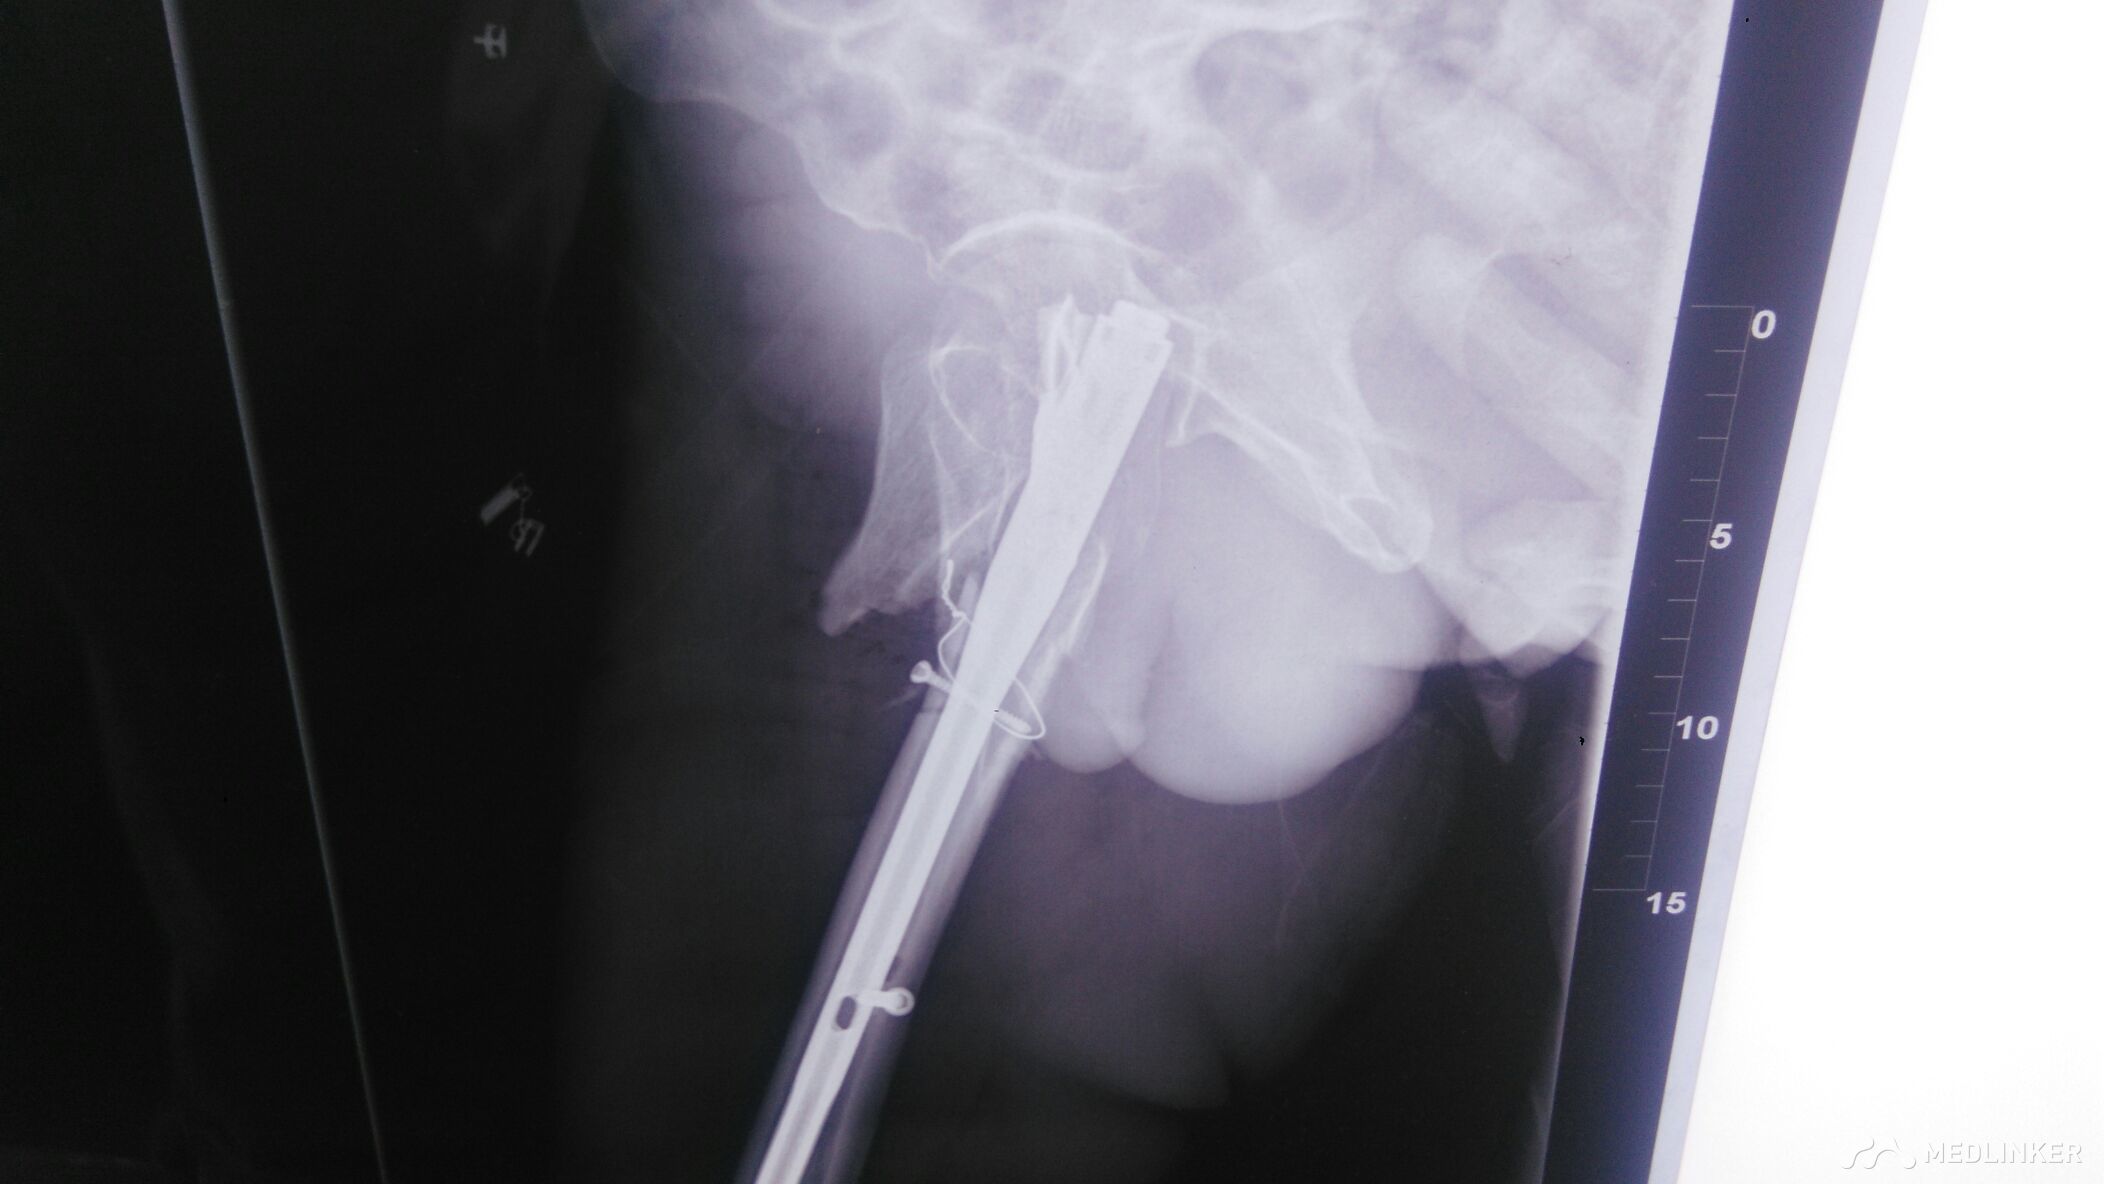

髋部手术。髋部畸形明显,肿胀明显。以股骨外侧为著。足部血运正常,感觉正常。

髋部手术,髋部肿痛,肿胀明显。压痛阳性,叩痛阳性。髋部活动受限。

沉痛的教训,下面的锁定,没有锁住,只能相当于阻挡钉。逼住主钉。髋部力线改变。防旋能力差。